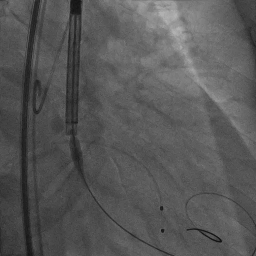

主动脉根部造影

患者取平卧位,局麻镇静,颈内静脉置入中心静脉置管,测中心静脉压3cmH2O,左侧桡动脉穿刺置管监测动脉压力。术区无菌消毒铺巾,穿刺右侧桡动脉并置入6F鞘管,超声引导下穿刺双侧股动静脉,右股动脉预置两把Proglide缝合器,左侧股动静脉留置6F鞘管。将Lunderquist加硬导丝送至升主动脉,沿加硬导丝送20F GORE动脉鞘管。将临时起搏漂浮电极经右股静脉送至右室心尖部位,测试起搏器工作良好。予肝素6000单位,ACT大于250s。经左股动脉置入6F猪尾导管,在释放体位下行主动脉根部造影。经右侧桡动脉送脑保护装置分别在左颈总动脉、头臂干动脉释放保护。经右侧股动脉送入6F JL4.0造影导管造影提示:左前降支未见明显狭窄,TIMI血流III级;回旋支未见明显狭窄,TIMI血流III级。送入6F JR4.0造影导管造影提示:右侧冠脉未见明显狭窄,TIMI血流III级。在AL2导管指引下,直头导丝跨瓣至左心室,沿导丝送猪尾导管至左心室,测得跨瓣压差50mmHg。经猪尾导管送入塑形后的加硬导丝送至左心室内,沿加硬导丝送启明L26主动脉瓣系统至主动脉瓣处,在释放体位下释放至工作状态,经猪尾导管行主动脉造影示瓣膜定位良好。继续完全缓慢释放瓣膜。送入20×40mm球囊至主动脉瓣,在180次/分起搏下,收缩压下降至50mmHg时行球囊扩张,扩张无明显腰征。主动脉造影示瓣膜支架膨胀良好,微量瓣周漏。撤出输送系统。经胸超声评估主动脉瓣位为人工瓣回声,位置固定,瓣叶活动良好。主动脉造影提示主动脉无夹层、出血。行造影提示腹主动脉、髂动脉、股总动脉未见明显异常,缓慢撤出20F大鞘管,缝合右侧股动脉穿刺点,保留右侧临时起搏器并固定良好。